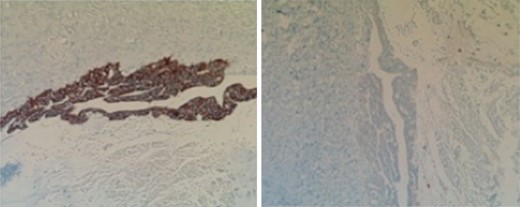

Subsequent surgical pathology results confirmed two separate malignant processes causing the carcinomatosis: Immunohistochemical examination was performed on the surgical specimens. The appendiceal tumor stained negative for CK-7 and positive for CK-20 (Fig. 1), whereas the ovarian sample stained positive for CK-7 and negative for CK-20 (Fig. 2), consistent with malignant processes of independent origins.

Perforated mucinous adenocarcinoma of the appendix arising from villous adenoma, at least 8.5 cm invading into subserosa and into adjacent ileal and cecal serosa with widespread involvement of omentum (carcinomatosis).